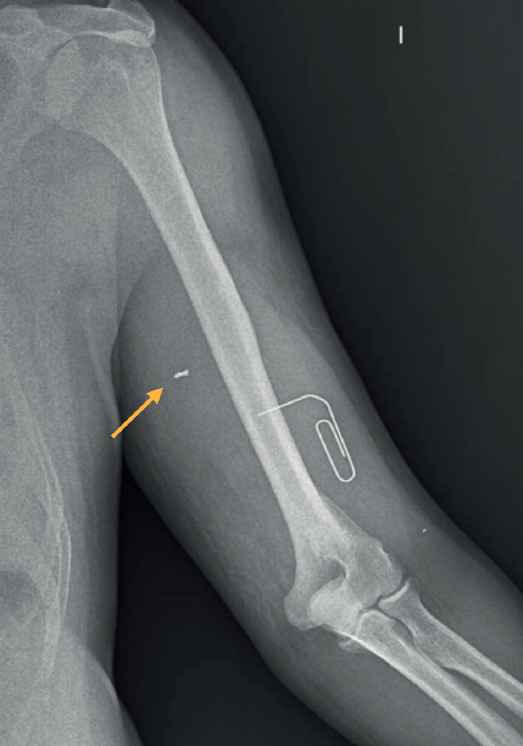

Se realiza una radiografía (Figura 1) y se observa la presencia de un cuerpo extraño. Se intenta la extracción, pero no es posible y el paciente es citado de manera urgente con Traumatología. En la exploración física ese día destaca la presencia una masa pulsátil en la cara medial del brazo, acompañada de parestesias en la palma de la mano.